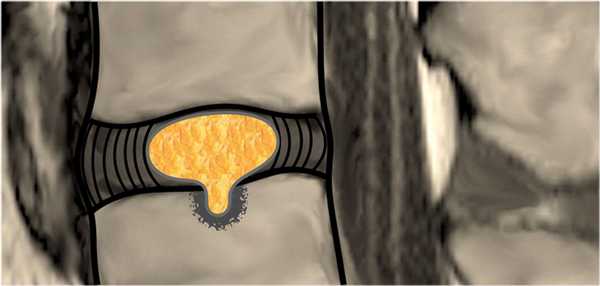

Грыжа диска - смещение диска за пределы границы межпозвонкового пространства.

Протрузия: ширина между краями грыжи диска, меньше ширины у основания грыжи.

Экструзия: ширина между краями грыжи диска, больше ширины у основания грыжи.